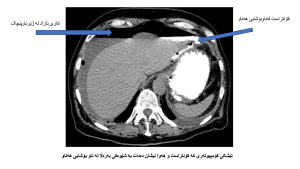

تیشککاری کۆمپیوتهری: به بێ رهنگ ههوا دهبینی له بۆشایی زگ، بهزۆریش ههواکه لای گهده و دوازدهگرێیه. ئەگەر کۆنتراست یان رەنگیش بەکاربێنی ئەوا رەنگەکە بە لە کۆنبەدەرکەوە دەچێتە ناو بۆشایی هەناو (سەیری وێنەکە بکە):